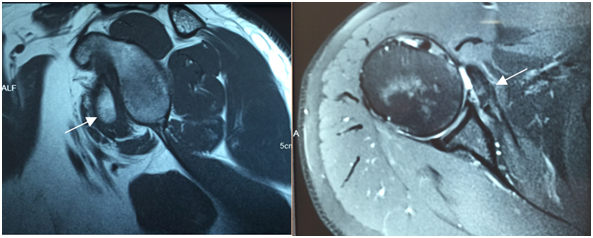

The patient underwent surgery in a beach chair position under general anesthesia and a brachial plexus block. Diagnostic arthroscopy was performed via a posterior port. The area of subscapularis insertion was examined in the superior-to-inferior direction at the anterolateral port. This showed that the medial biceps pulley system was injured and the long head of the biceps was medially dislocated, but that there were no other intra-articular injuries. After creating the anterior and anterolateral ports, the fragment adherent to the adjacent soft tissues was observed as a single large fragment that included the subscapular insertion. The axillary nerve was identified at the exterior face of the subscapular tendon, deep and medial to the conjoined tendon. Caution was taken not to damage the nerve during the release procedure. The fragment was then released circumferentially. After provisionally tying an Ethibond® thread on the subscapular tendon to aid mobilization and with the arthroscope in the anterolateral port, tendon traction was facilitated by radiofrequency-based debridement and a soft tissue shaver to debride the external and internal surfaces of the tendon, respectively. This resulted in sufficiently mobilizing the fragment so that it could reach its anatomical location. Next, with the arthroscope in the posterior port, we performed cruentation of both the internal surface of the free fragment and of the area of reinsertion of the lesser tuberosity, taking care to remove the fibrotic tissue without removing any bone. Fragment reattachment was done in the same manner as a subscapular tendon repair (Figure 3), except for the need to use a third anchor at the lateral margin of fracture site to settle the bone fragment.

Figure 3 Intraoperative images.

From left to right, initial aspect of the lesser tuberosity adhered to soft tissue, the aspect after debridement and mobilization, passage of sutures using "Bird Beak", partial reduction of the fragment and final appearance after final fixation with 3 anchors. The first suture anchor was placed in the inferior region of the medial margin at the fracture site, with the subscapularis tendon penetrated immediately adjacent to the bone-tendon interface at the most inferior aspect, using a bird-beak passer. The second anchor was placed in the medial margin of the fracture area in a more superior position, with the suture passing through the most superior aspect of the subscapularis tendon. The third anchor was placed in the most lateral aspect of the fracture area and its suture threads were passed through the bony fragment of the lesser tuberosity to ensure its fit in the fracture area. In addition, the threads of this third anchor were used to perform tenodesis of the long head of the biceps. Tenotomy was only performed after the bone repair and tenodesis. Checking was done through the anterolateral port. In the immediate postoperative period, the shoulder was immobilized with a sling for four weeks before the patient started physiotherapy. It has now been two and a half years since the operation and the patient has shown significant improvement. Of note, the DASH score decreased to 8.3, the UCLA Shoulder Score increased to 34, the SF-36 Score increased to 83.8 and the VAS score decreased to 2. All clinical tests for subscapularis lesions were negative at the most recent evaluation (Figures 4 & 5).